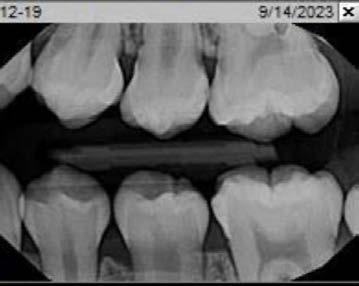

Technique for extracting tooth or root tip from underneath fixed partial denture emphasizes use of magnification from dental loupes or dental surgical operating microscope for precision when performing technique-sensitive procedure. Case report.